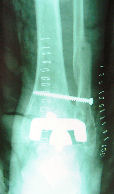

Osteotomia tibial

Na sua vertente preventiva, consiste na correcção das deformidades ósseas ou músculo-tendinosas (Osteotomias, Enxertos ou Plastias) que propiciam o aparecimento de Artrose. Estas cirurgias não são, infelizmente, tão frequentes como deviam, porque incidem sobre o doente ainda sem Artrose ou com esta numa fase inicial. Como os sintomas são poucos ou nenhuns, muitas vezes o mesmo recusa uma cirurgia nesta fase!

Na sua vertente paliativa, é o tratamento de último recurso para a Artrose. Consiste em fusão articular (Artrodese), remoção das superfícies articulares parcial ou totalmente (Resecção) ou mais moderna e frequentemente, na aplicação (Artroplastia) de uma articulação sintética: a Prótese Articular.